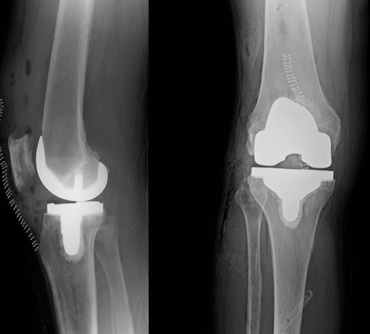

Jon Conroy Orthopaedics is proud to lead the way in robotic surgery in Abu Dhabi and Dubai. Using advanced robotic-assisted technology, we enhance the accuracy and consistency of hip and knee replacements, minimising errors in bone preparation and implant placement to deliver safer, more reliable outcomes for our patients.

The state-of-the-art Mako™ robotic arm system works alongside the surgeon from the pre-surgery planning stage through to assisting in the surgery itself in order to improve the accuracy and precision of the procedure.

It provides patients with a personalised surgical plan for joint replacement surgery as before surgery, a personalised 3D model is created based on the patient’s own CT scan, allowing the exact size and orientation of the hip or knee implant to be planned.

During the operation, the robot arm guides the surgeon, following the customised pre-surgery plan, reducing the risk of surgical errors in bone preparation and placement of the implants.

The Mako Robotic system supports the consultant throughout orthopaedic surgery. Robotic Arm Assisted surgery for a total hip replacement has been shown to be more accurate and to offer a greater improvement in patient function when compared to manual surgery. It can be used for partial knee replacement, a surgical procedure that helps relieve the pain caused by osteoarthritis (the wearing out or breakdown of cartilage in the joints in the knee), as only the damaged area of the knee joint is replaced, helping protect the healthy bone and tissue.

When the surgeon prepares the bone for the implant, the Mako System guides the surgeon within the pre-defined area and helps prevent the surgeon from moving outside the planned boundaries. This helps provide more accurate placement and alignment of your implant.